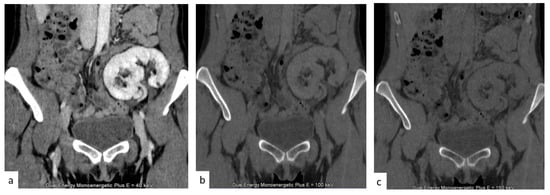

Virtual unenhanced images (Figure 8) enable the omission of the true unenhanced scans, with an up to 50% dose reduction, when applied to the split bolus contrast administration technique, while maintaining the diagnostic value of the exam [53].

Figure 8.

(a) Nephrographic phase of a transplanted kidney. (b,c) Two virtual non-contrast images at 100 (b) and 150 (c) KeV.

Virtual non-contrast images allow the identification of calculi and hemorrhagic changes and help in the characterization of renal masses, but without the acquisition of a distinct unenhanced phase, thus limiting the radiation dose [54,55].